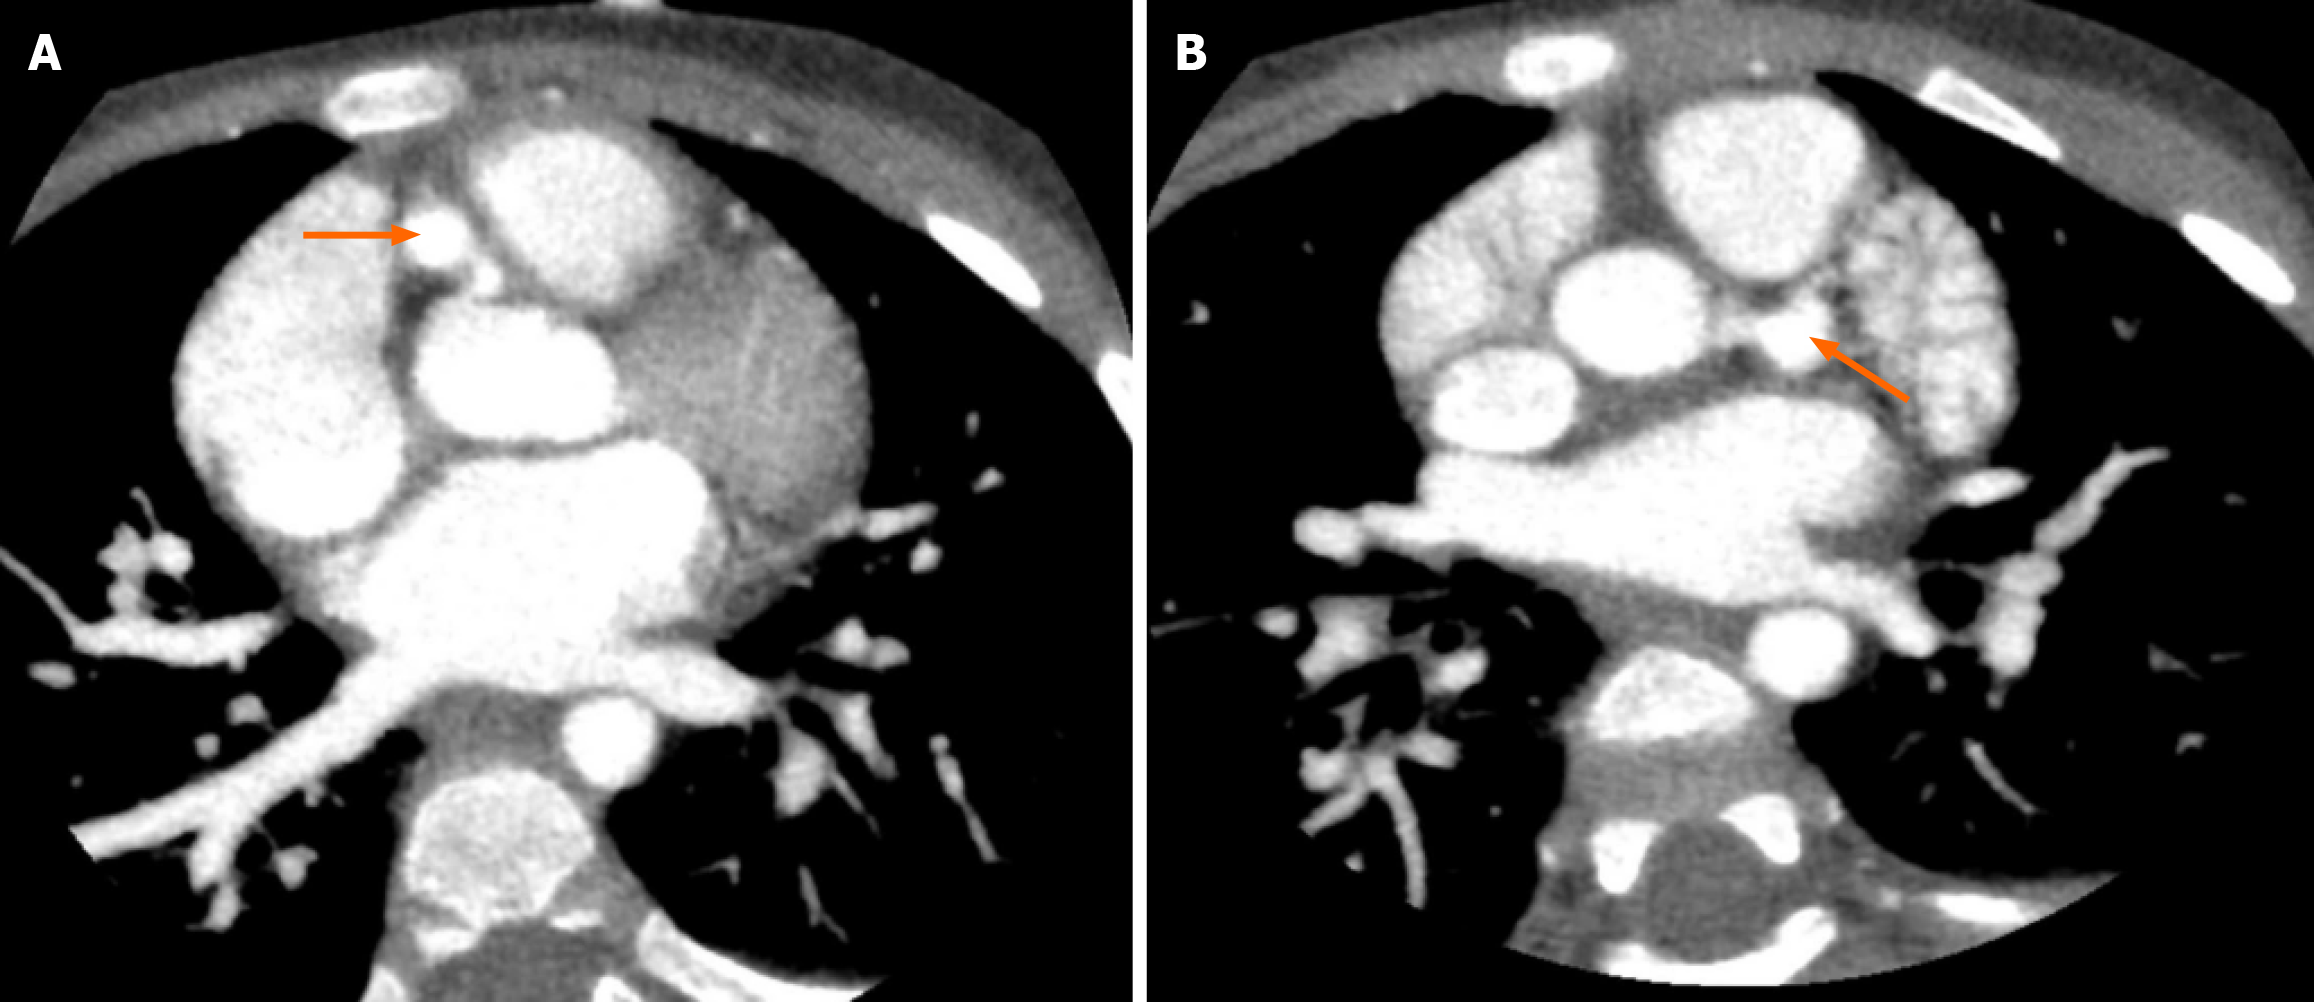

Figure 4 Contrast-enhanced computed tomography scans of the coronary arteries, with orange arrows indicating the dilated coronary artery.

A: Right coronary artery; B: Left coronary artery.